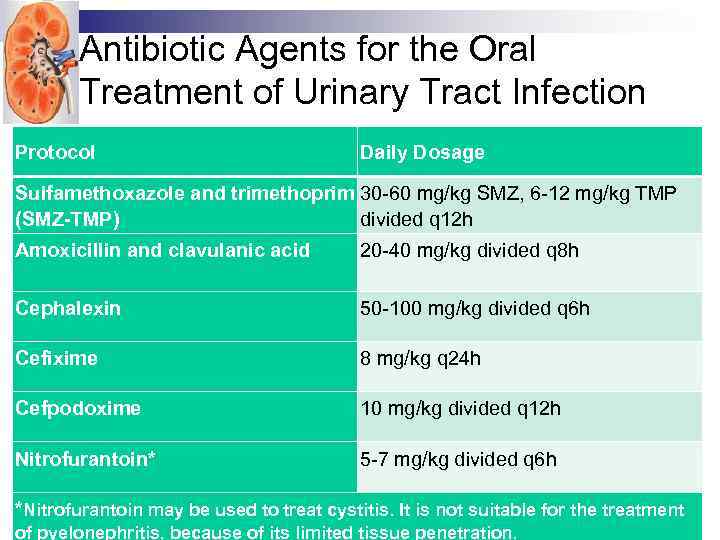

Antibiotic Agents for the Oral Treatment of Urinary Tract Infection Protocol Daily Dosage Sulfamethoxazole and trimethoprim 30 -60 mg/kg SMZ, 6 -12 mg/kg TMP (SMZ-TMP) divided q 12 h Amoxicillin and clavulanic acid 20 -40 mg/kg divided q 8 h Cephalexin 50 -100 mg/kg divided q 6 h Cefixime 8 mg/kg q 24 h Cefpodoxime 10 mg/kg divided q 12 h Nitrofurantoin* 5 -7 mg/kg divided q 6 h *Nitrofurantoin may be used to treat cystitis. It is not suitable for the treatment of pyelonephritis, because of its limited tissue penetration.

Antibiotic Agents for the Oral Treatment of Urinary Tract Infection Protocol Daily Dosage Sulfamethoxazole and trimethoprim 30 -60 mg/kg SMZ, 6 -12 mg/kg TMP (SMZ-TMP) divided q 12 h Amoxicillin and clavulanic acid 20 -40 mg/kg divided q 8 h Cephalexin 50 -100 mg/kg divided q 6 h Cefixime 8 mg/kg q 24 h Cefpodoxime 10 mg/kg divided q 12 h Nitrofurantoin* 5 -7 mg/kg divided q 6 h *Nitrofurantoin may be used to treat cystitis. It is not suitable for the treatment of pyelonephritis, because of its limited tissue penetration.